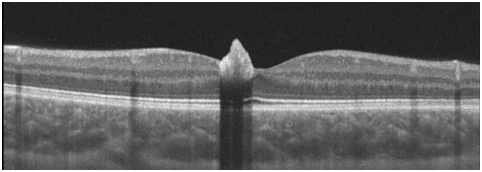

The OCT demonstrated that the lesion’s surface was hyper-reflective with distinct borders and significant underlying shadowing, which prevents a detailed evaluation of outer retina/ choriocapillaris. No Inner/Outer retinal alterations of adjacent retina and fluid are visible at OCT images (Figure 3). A star shaped fovea and a possible minimal vitreo-macular traction is visible in the reconstruction of the macular surface of the right eye. (Figure 4). Clearly visible if compared to normal foveal excavation of the fellow eye (Figure 5). In the OCT-A we observed a mild intralesional vascularization, not visible by SD-OCT scans or slit lamp examination, both in the superficial and deep capillary plexus (Figure 6). Indeed, foveal hypo-reflectance for masking effect in Outer retina and Choriocapillaris layers at OCT-A was recorded (Figure 7A&B).

Figure 3 OCT Lesion’s surface was hyper-reflective and demonstrated distinct borders Significant underlying shadowing, which prevents a detailed evaluation of outer retina/ choriocapillaris.

The avulsion is a specific complication of CSHRPE. In literature, two pathogenetic hypothesis have been formulated. The first hypothesis is that a single or a group of RPE cells migrated to the retinal surface during embryogenesis and then proliferated into an hamartomatous lesion that did not involve the full retinal thickness . The second possibility comprises RPE cell migration, due to traction created by this lesion.9 Our case presents an avulsion without vitreo-macular traction. The avulsion was clearly visible at SD-OCT (Figure 3). In our case the SD-OCT scans did not show signs of vitreous-macular tractions. Conversely, Barns et al decribed a case of CSHRPE with avulsion, severe vitreo-macular traction and tractional oedema.9 Despite there was no signs of vitreomacular traction at SD-OCT, in the reconstruction of the macular surface of the right eye there was star shaped fovea and a minimal gliosis with a Internal Limiting Membrane (ILM) minimum involvement (Figure 4). Furthermore, OCT-A showed a mild intralesional vascularization not visible by SD-OCT scans or slit lamp examination, both in the superficial and deep capillary plexus (Figure 6A&B).